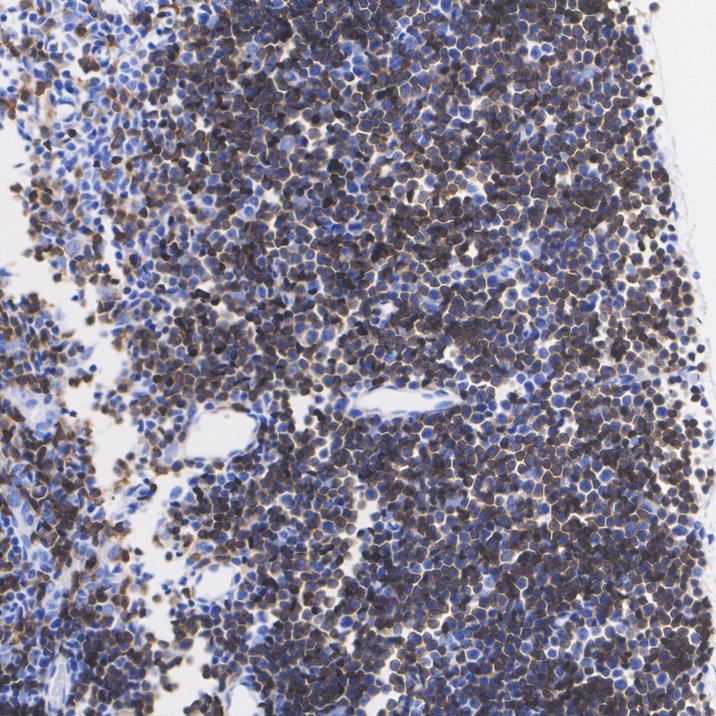

Catalog# HA722966

CD4 Recombinant Rabbit Monoclonal Antibody [PSH08-22]

IHC-P